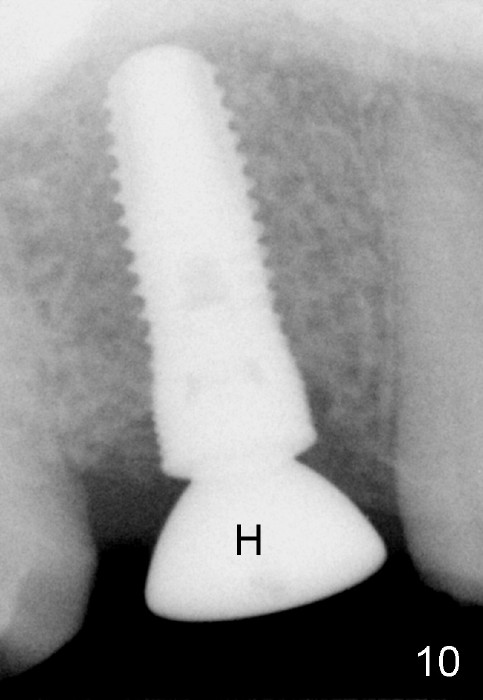

The bone density (Fig.1 white *) at the edentulous area (#3) is lower than that at the dentulous one (black *, 50 year-old man). The buccal plate is also atrophic and concave (Fig.2,3 arrowheads). A series of bone expanders are used to form osteotomy (following 1.6 mm pilot drill) at the depth of 14 mm (Fig.3 E 3.0 mm in diameter). When the last expander (4.3 mm) is removed from the osteotomy, the buccal plate appears to have been moved buccally (Fig.5 arrowheads). A 5.3x14 mm submerged implant (Fig.6 I) is placed with insertion torque >35 Ncm. The buccal plate seems to improve following placement of an 8.2 mm healing abutment and suturing (Fig.7). No bone graft is used. The buccal plate remains normal 12 days postop (Fig.8). It is slightly concave 3 months postop (Fig.9) with minimal bone resorption at the crest (Fig.10 (H: healing abutment),11 (A: cemented abutment). Nine months post cementation (12 months postop), bone resorption at the crest remains minimal (Fig.12) while the buccal plate (Fig.13 *) at #3 remains strong. Bone loss appears not to get worse 22 months post cementation (Fig.14). Soft and hard tissues remain healthy around the implant crown 3 years (Fig.15) and 3.5 years (Fig.16,17) post cementation.